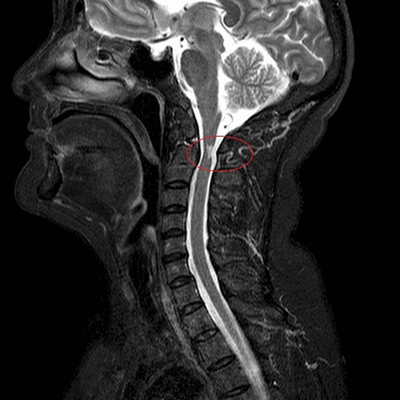

МРТ шеи: перелом зубовидного отростка с невральной компрессией (сагиттальная плоскость, Т2 последовательность, STIR)

МРТ позвоночника назначают, если предыдущие способы обследования - КТ, рентгенография, УЗИ с допплером - продемонстрировали неоднозначные результаты или характер выявленных изменений требует уточнения, для оценки индивидуальных анатомических особенностей перед планируемой операцией, в рамках динамического наблюдения за болезнью на фоне лечения. Что показывает МРТ шеи:

МРТ шейного отдела позвоночника: оценка лордоза, сагиттальная плоскость, Т2 последовательность

- искривления позвоночника - кифоз, лордоз, сколиоз;